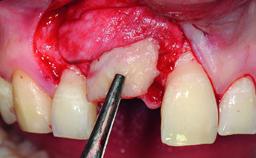

A 15-year-old male patient was referred to us by his pediatric dentist in June 2004 for evaluation of treatment options for his failing tooth 21. The patient had recently seen an endodontist for internal bleaching and been advised that there had been significant resorption and ankylosis. The patient’s mother was concerned because the tooth appeared shorter than the adjacent one. His past dental history was significant for trauma (September 2001), where the tooth had been avulsed and reimplanted. Teeth 11 and 21 had been endodontically treated.

| Bone Volume | Deficient horizontally, requiring prior grafting |